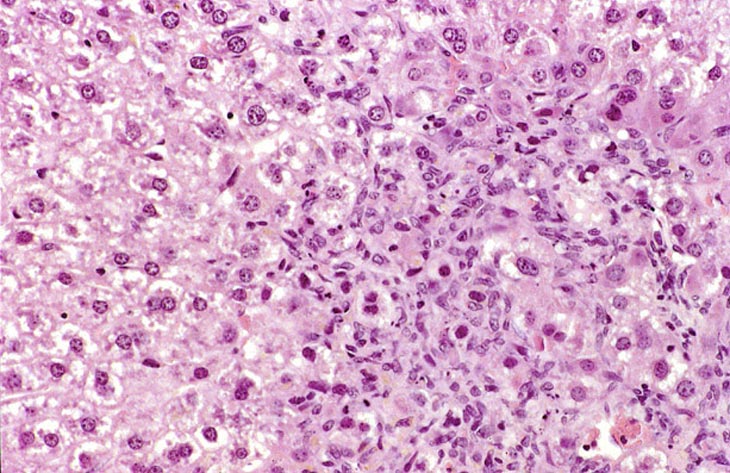

Visit the NTP WebsiteThis change was originally diagnosed as endothelial cell proliferation. Based on the H&E stained sections, it is not possible to definitively identify the proliferating sinusoidal lining cells as endothelial cells but some have cytomorphological features consistent with endothelial cells. Low and high magnifications of endothelial cell hyperplasia.